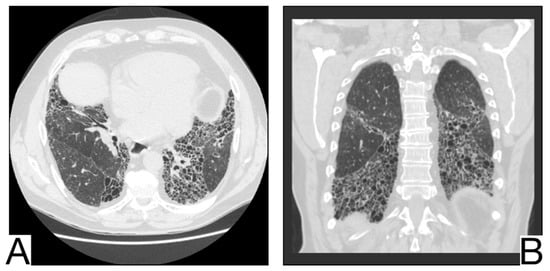

1. Early phase/Stage 1—days 0–4. Ground glass opacities represent the main radiological characteristic [] (Figure 4A);

Figure 4. Imagistic findings in COVID-19 (A). Multiple areas of ground glass infiltration (patient on the third day of symptoms) (B). Bilateral patches of ground glass and subsegmental consolidation (C). Ground glass and consolidation with air bronchogram (8 days after onset) (D). Diffuse ground glass infiltration (white lung appearance). Note. Adapted from Hefeda et al. (2020) [].

2. The progressive phase/Stage 2 refers to days 5–8, and the hallmark is a cobblestone appearance (Figure 4B) coexisting with extensive ground-glass opacities and condensation foci [];

3. Peak phase/Stage 3 is typical for days 9–13, and CT shows pulmonary condensations (Figure 4C), sometimes surrounded by a halo of ground glass.

4. The absorption phase/Stage 4 begins around day 14; areas of ground glass together with linear condensations are appreciable (Figure 4D).